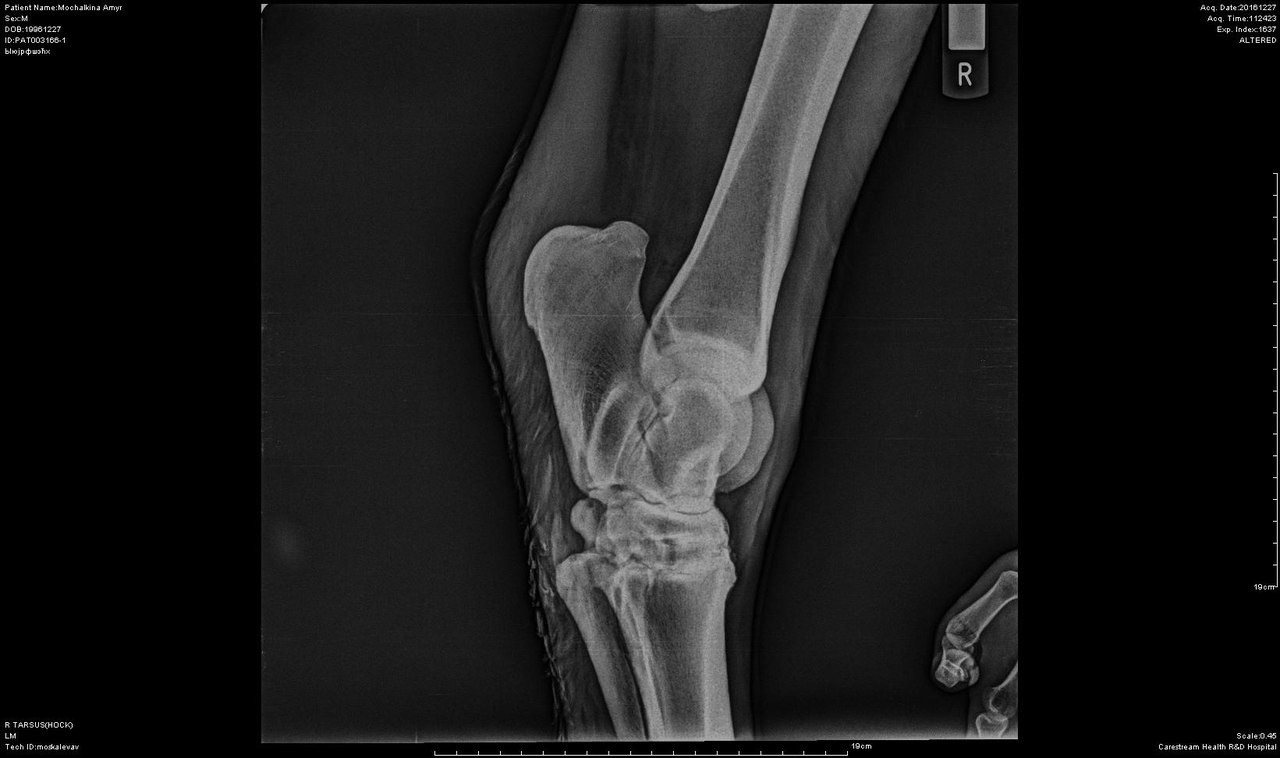

В анамнезе у коня остеоартроз правого скакательного сустава и левого путового на тазовой конечности (диагноз подтвержден рентгенологически в декабре 2016 г.), имеется выраженная хромота, никаких верховых нагрузок Амур не несет и нести не сможет.